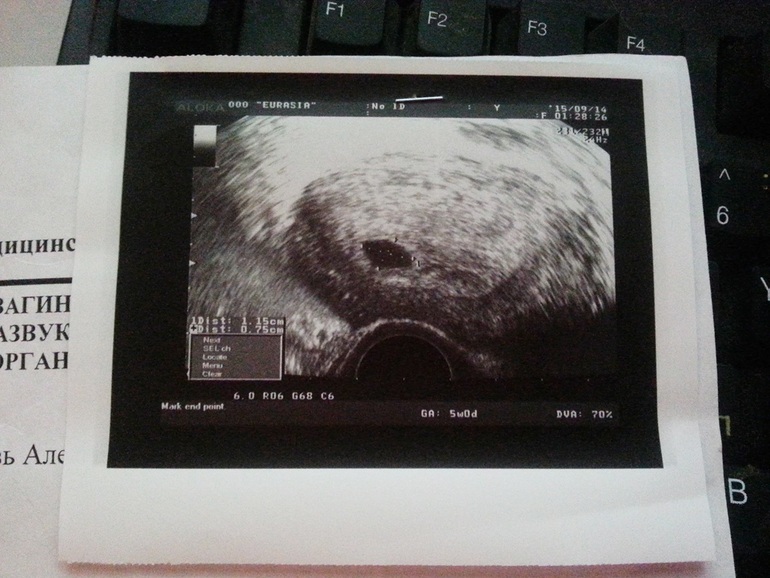

Через полторы недельки пошла на узи, гиня в платной клинике(там я наблюдалась уже год) поставила 5 недель ровно(14 сентября)